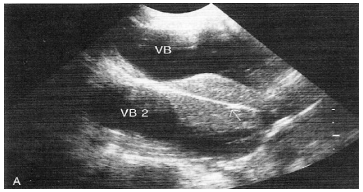

Em uma análise ultrassonográfica, a presença de artefatos se refere à exibição e às informações que não transmitem exatamente a verdadeira imagem da área examinada. A informação gerada pode ser errônea, superficial ou deslocada. É importante reconhecer esses artefatos, a fim de evitar falsas interpretações. Analise a figura a baixo.

O tipo de artefato corresponde à